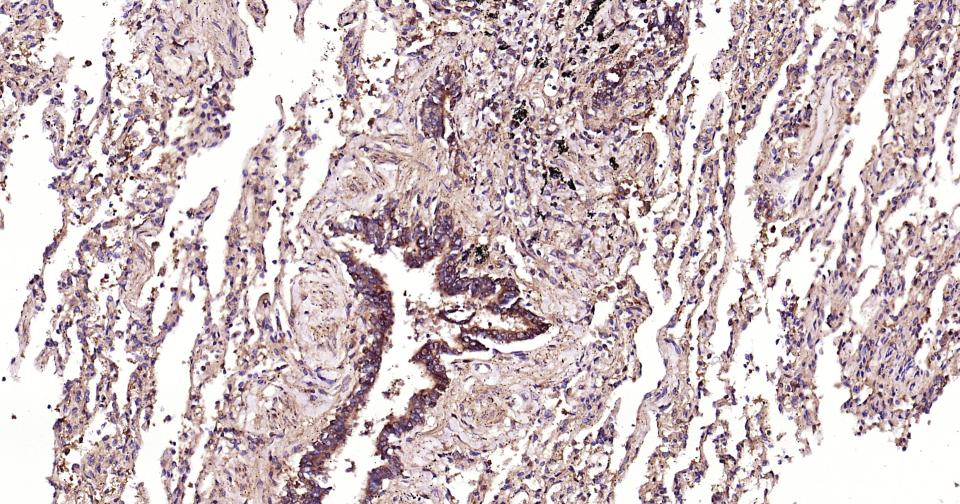

Paraformaldehyde-fixed, paraffin embedded Human Breast Cancer; Antigen retrieval by boiling in sodium citrate buffer (pH6.0) for 15 min; The section was incubated with SCF  Monoclonal Antibody, Unconjugated (bsm-61250R) at 1:200 overnight at 4°C, followed by conjugation to the bs-0295G-HRP and DAB (C-0010) staining.